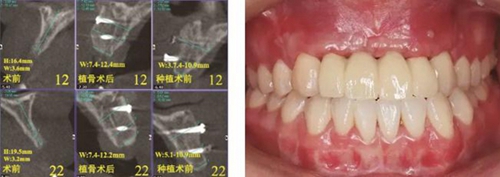

(1)2014年1月:初診明確診斷為12、11、21、22缺失,缺牙區(qū)牙槽嵴較薄,拍攝CBCT(kavo卡瓦,德國(guó))顯示:缺牙區(qū)存在水平向骨缺損,12位點(diǎn)可用牙槽骨高度為16.4mm,寬度為3.6mm;22位點(diǎn)可用牙槽骨高度為19.5mm,寬度為3.2mm,唇側(cè)骨板稍有凹陷,明確治療計(jì)劃。

夠骨面,使用骨鑿等取骨器械制取骨塊,填塞明膠海綿,分層縫合。口內(nèi)切開植骨區(qū)粘膜,翻瓣,充分暴露待植骨區(qū),用裂鉆在受骨區(qū)骨面預(yù)備若干滋養(yǎng)孔,修整骨塊,以器械夾持骨塊置于手術(shù)受植骨區(qū)并緊貼骨床,使用鈦釘牢固地固定骨塊,植骨塊間的間隙用自體骨屑及少量骨粉(Geistlich Bio-Oss,瑞士)混合后充填,充分減張后嚴(yán)密縫合創(chuàng)口。告醫(yī)囑,囑患者術(shù)后幾天盡量臥床休息,十天后拆線。拍攝CBCT示:牙槽嵴寬度擴(kuò)增明顯:12位點(diǎn)擴(kuò)增至7.4mm-12.4mm,22位點(diǎn)擴(kuò)增至7.4mm-12.2mm。

圖17 CBCT測(cè)量骨量變化 圖18 早期修復(fù)戴牙當(dāng)天